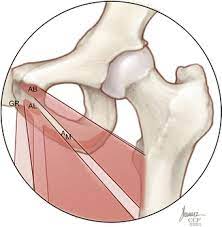

Adductor tenotomy in Cerebral palsy patients for prevention of HIP migration – outcome and predictors of treatment success In the Netherlands.

GRIPP

Golf Related Injury Prevention Program (GRIPP) intervention.

GUIDed growth of the proximal femur to prevent further hip migrAtion iN CErebral palsy patients